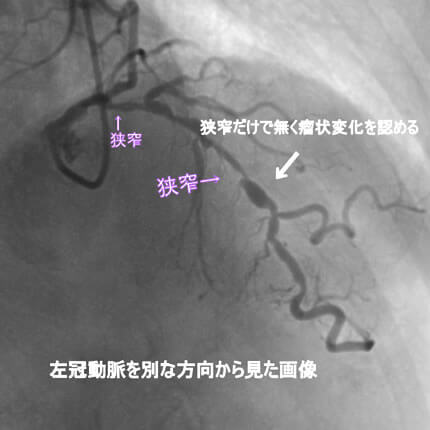

危険因子が特に複合的にあると動脈硬化は加速します。今回は、動脈硬化が加速するとどうなるか、実際の症例でお示しします。なお、お見せします画像は、すべて動画から静止画像にしています。実際には冠動脈造影は動画で見ます。

また、動脈硬化は冠動脈だけに生じる訳ではないことも示したいと思います。冠動脈に病変がある方は他の動脈にも強い動脈硬化を認めることが多いのです。具体的には腹部大動脈瘤、胸部大動脈瘤、脳梗塞、脳出血、下肢動脈閉塞などを合併します。逆にこれらの病気が見つかってそれから冠動脈疾患が見つかることも結構あります。血管は三次元構造なので色々な方向から撮影して血管形態を確かめます。同じ血管を左右上下や斜め方向から撮影します。

1番目の患者さんは80歳の男性です。この方の危険因子は高血圧、高脂血症、喫煙です。この方の冠動脈造影と腹部CT画像を示します。図1-1から1-8の画像は全て全てこの患者さんの画像です。

よく解らないと思いますが、冠動脈に多数の狭窄があることと冠動脈が「こぶ状変化(医学用語で瘤状変化)」を生じているのが解ると思います。

参考までに、これを医学記号で表すと、下記のようになります。

「#1: 50% #2 :50% #3 #4PD #4AV:75% #5 50% #6 75% #7 75% #8 #9 #10 #11 #12 」

#1 、#2 などの数字は冠動脈の部位を表します。50%というのは正常の50%が狭窄しているという意味です。